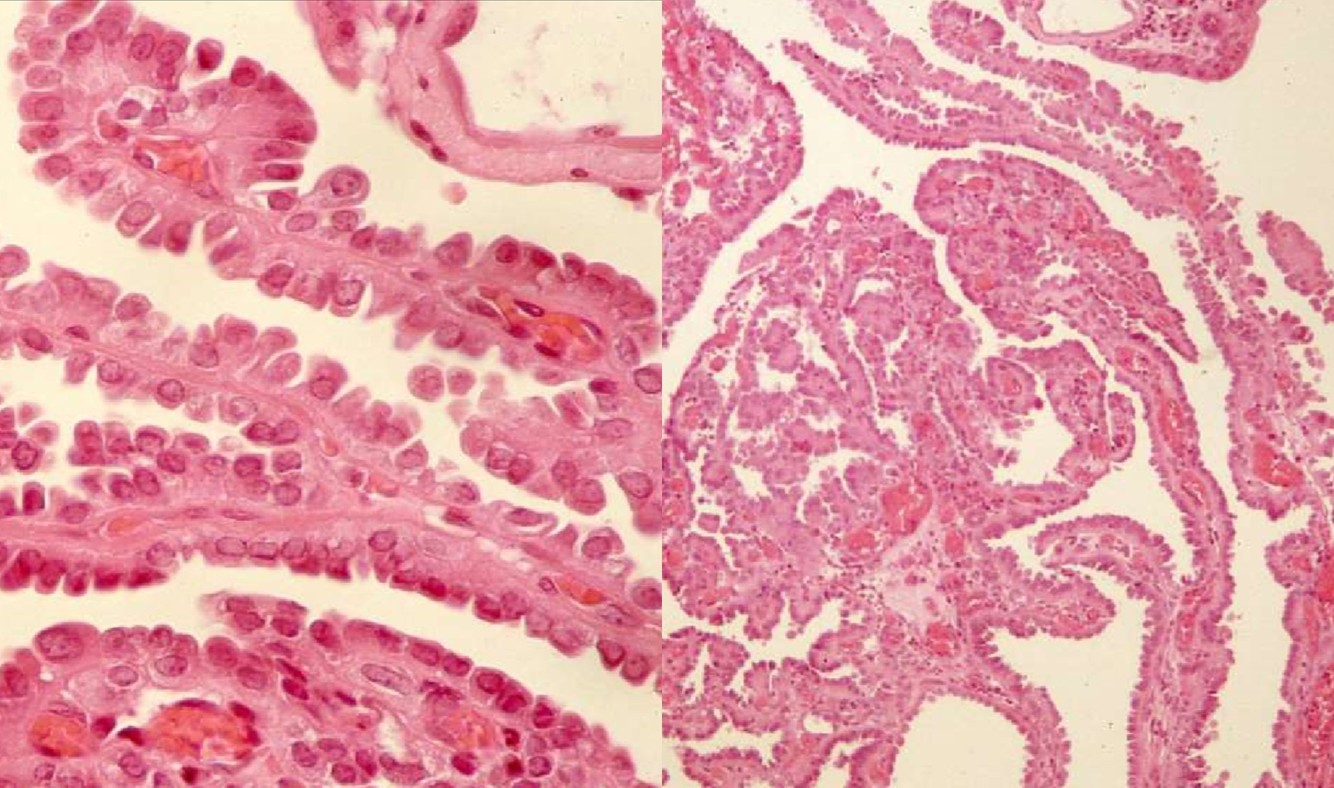

PAPILLARY RCC

- Type 1

- small cells, clear to basophilic cytoplasm, single layer of small oval nuclei, inconspicuous nucleoli

- foamy macrophages and/or edema, psammoma bodies and calcium oxalate crystals

- low grade

- Type 2

- large cells, abundant eosinophilic cytoplasm, pseudostratified or apical large spherical nuclei, prominent nucleoli

- macrophages, edema, psammoma bodies

- high grade

- Cytogenetics: 7+, 17+, Y-

- Better prognosis than clear cell RCC

- Positive stains: CK7, Rasimase